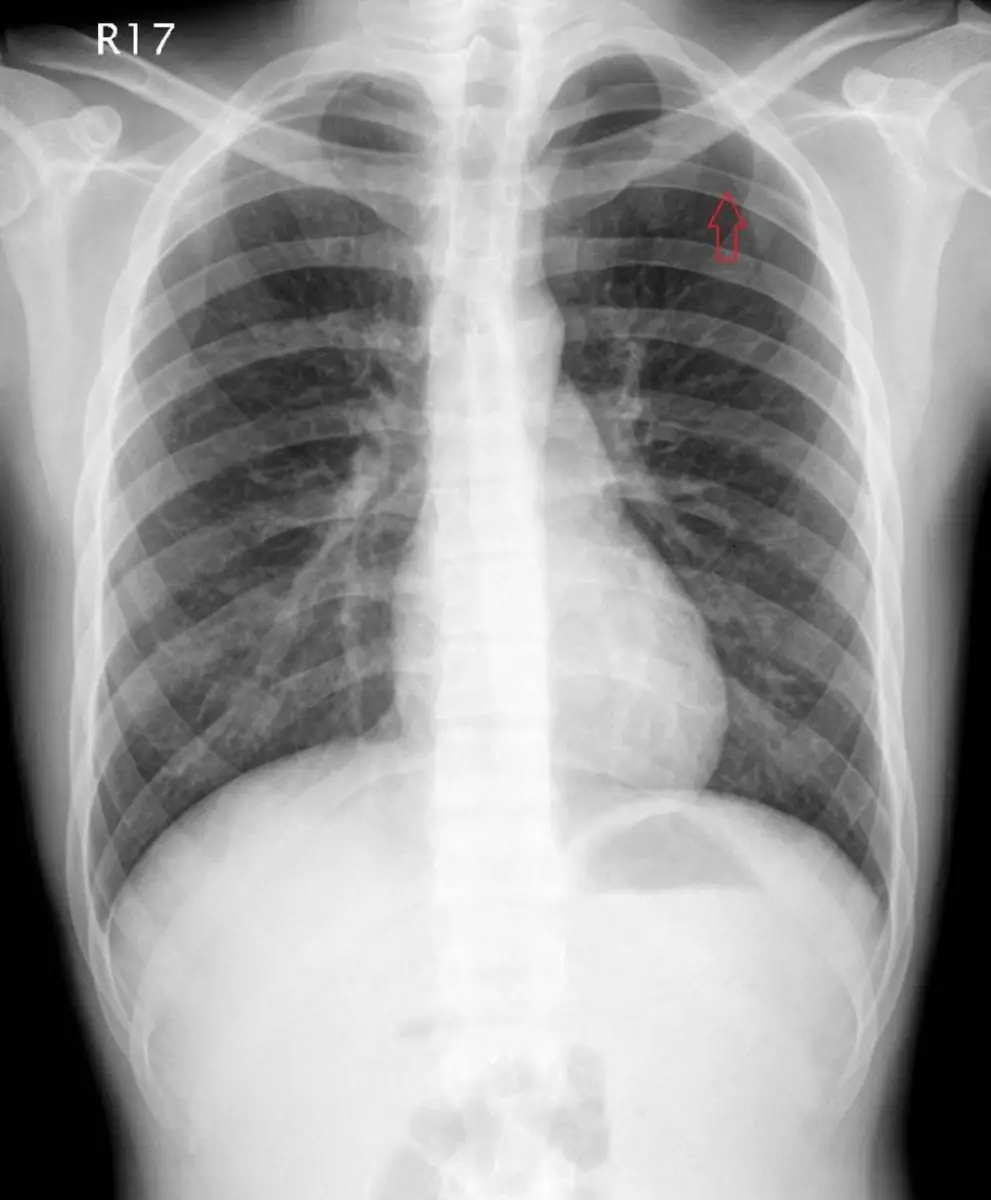

18歲男性無特殊疾病,某天在打籃球時突然胸痛、胸悶來到急診。胸部X光如附圖,下列何者為是:

胸部正位X光可見右上肺尖區透亮度異常增加,靠近胸壁處出現一條清晰的實線(箭頭所指),為肺緣(visceral pleural line);線外側無肺紋理顯示存在自由氣體。此征象典型於氣胸,使肺部分塌陷。未見液平面或其他肺實質病變。